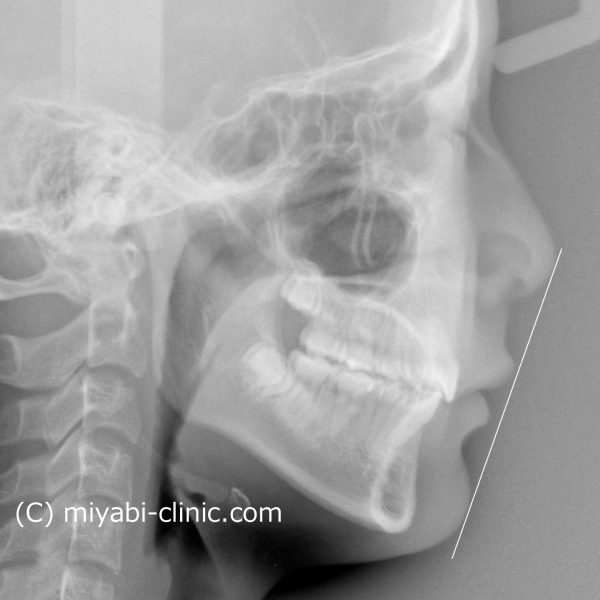

噛めない!「 手術しないで治してほしい 」18歳 男性 骨格性開咬

18歳の 男性です

「 噛めないので、治してほしい 」との事で来院されました。

骨格的な 開咬の状態で、顎が下方向に 開いてしまっています。

レントゲン写真で確認すると、顎が閉じる方向に回転して 開咬が治っています。

写真からは 判りにくいですが、

下あごが閉じるように 変化しています。